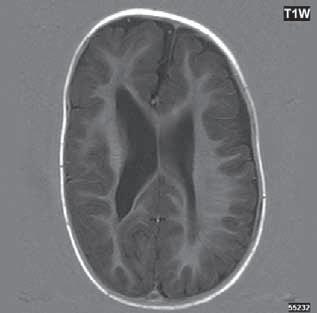

Obr. I.1.2a Paralelní postavení postranních komor, kolpocefalie, ageneze corpus callosum

Obr. I.1.2b Ageneze corpus callosum

Při agenezi corpus callosum CT i MR zobrazí paralelní průběh postranních mozkových komor (oproti fyziologickému

konvergentnímu průběhu) a jejich oddálení, časté rozšíření okcipitálních rohů – colpocefalie, někdy středočárový lipom, cystu. Koronální řezy ukážou rozšíření frontálních rohů postranních komor, III. komora je situována vysoko mezi postranní komory, tvoří jakoby trojzubec, který někteří autoři přirovnávají k přilbě Vikinga. Není patrné septum pellucidum. Častá je přítomnost středočárového lipomu nebo cysty.

Na vnitřní straně postranních komor pozorujeme v T2W obrazu poněkud tmavší strukturu než okolní myelinizovaná vlákna (naopak v T1W obrazu zvýšený signál), Probstovy provazce, axony, které za fyziologických okolností přecházejí přes corpus callosum do kontralaterální hemisféry.

Sagitální řezy nám přinášejí nejvíce informací o corpus callosum. Pozorujeme radiální průběh mozkových sulků ke stropu III. komory na vnitřní straně mozkových hemisfér a naopak nezobrazíme gyrus cinguli. Při parciální agenezi je postiženo především splenium.